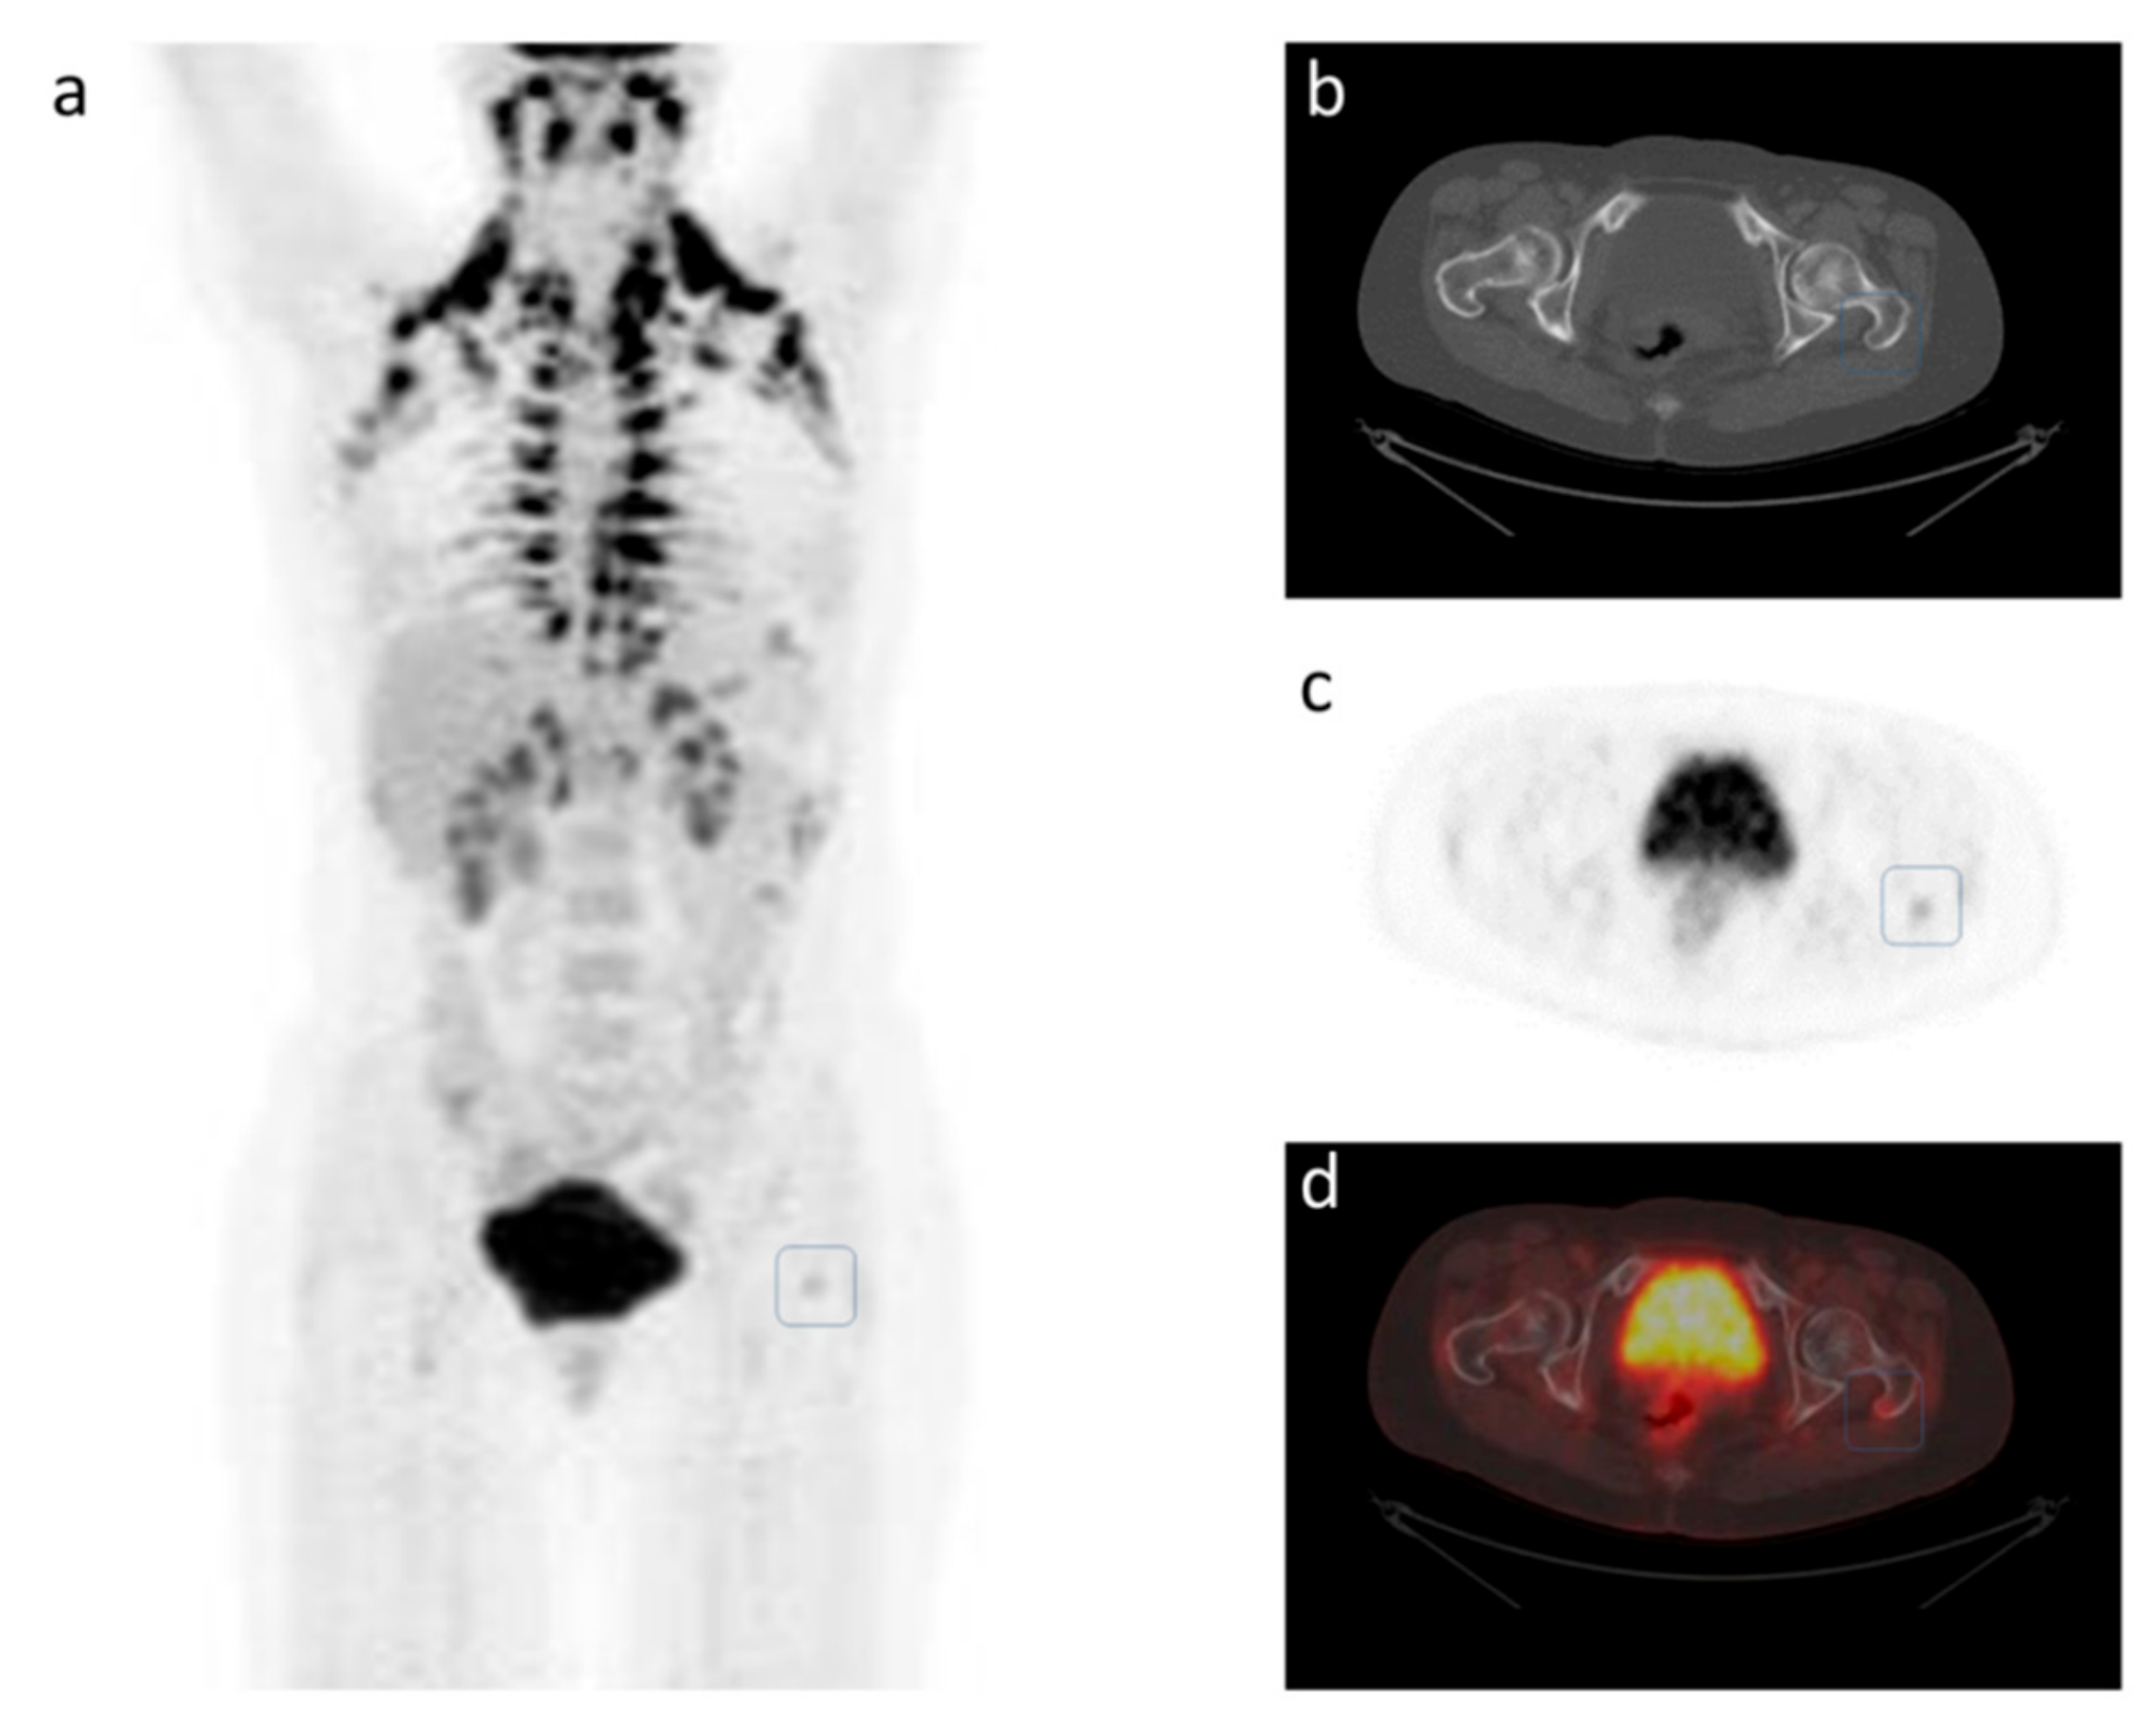

3. Response Prediction and Response Monitoring

4. A Case Study of Longitudinal Response Monitoring in Metastatic Breast Cancer